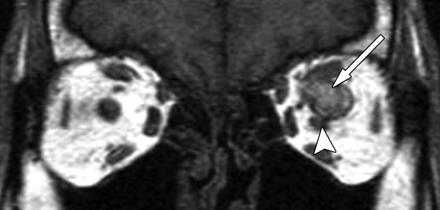

Аксиальное Т1-взвешенное изображение с контрастным усилением: асимметричное утолщение сосудистой оболочки глаза справа (стрелка) по сравнению с левой стороной.